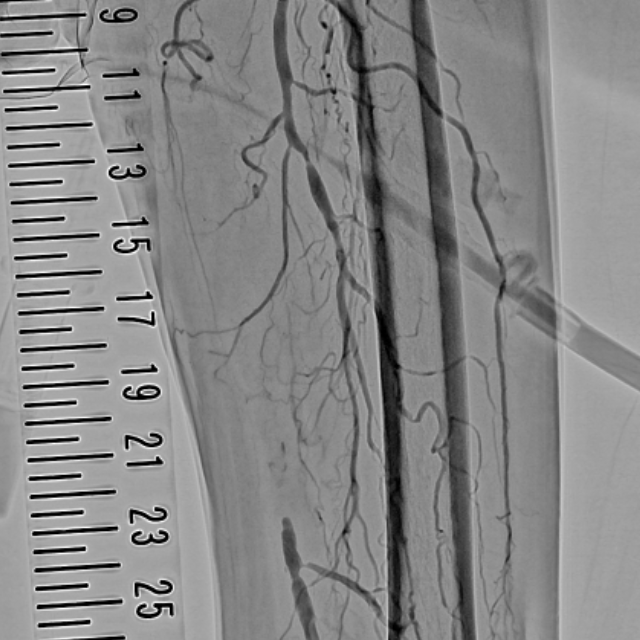

四肢血管撮影

四肢の血管造影では、腕や足などの動脈硬化などで狭くなった血管に対してカテーテルを挿入し風船やステント等で狭窄部位を拡張し、抹消への血流を改善する治療を行います。

左下肢動脈造影

左浅大腿動脈閉塞

術後動脈造影